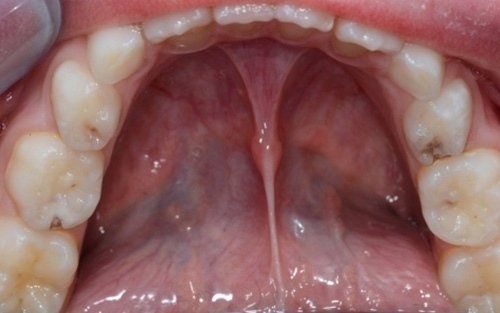

Spesso i dentini da latte cominciano a cariarsi già appena erompono nel cavo orale in quanto sono frequentemente a contatto con zuccheri semplici, come quelli veicolati dal biberon. Particolarmente aggressivi per i denti da latte risultano: tutte le tisane/infusi in commercio in bustine già pronte e pre-zuccherate; il latte zuccherato con qualsivoglia tipologia, incluso il miele; il latte e biscotti, specie nell’uso notturno; l’utilizzo quotidiano, spesso al posto dell’acqua, di succhi di frutta o bevande acide, per citare alcuni fra i più comuni errori commessi nel tentativo di dare una alimentazione completa al bambino, che spesso si traduce nella comparsa di una patologia chiamata